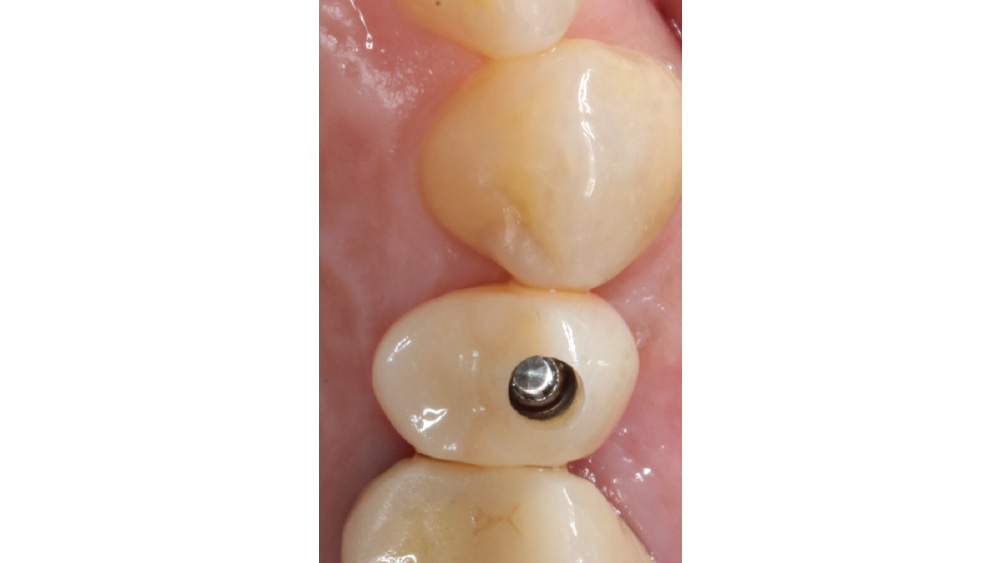

CASE REPORT

The following case, which I performed alongside Dr. Stephanie Tilley of Pensacola, Florida, illustrates the use of both surgical techniques for the same patient, who presented with edentulous spaces in the areas of both right and left maxillary first bicuspids. Due to varying soft-tissue volume on each side of the arch, implant surgery was performed using a flapless procedure for one site, while the attached gingiva was reflected to expose the available hard tissue for the other. As a result of proper site evaluation, treatment planning and restorative-driven implant placement, both surgical techniques led to successful outcomes for the patient.